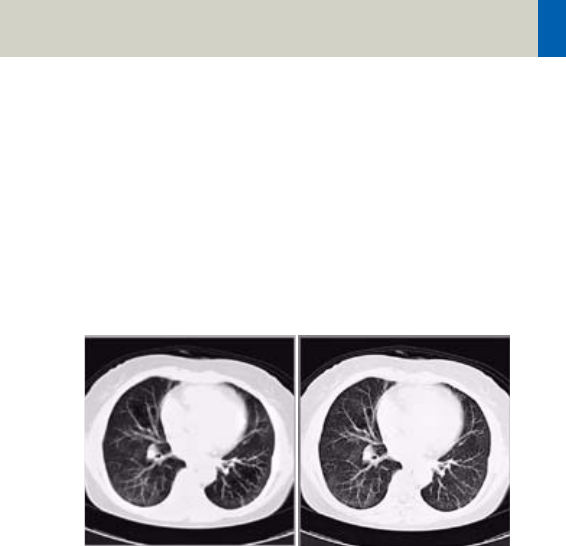

Head image without

correction.

Head image with

corrections.